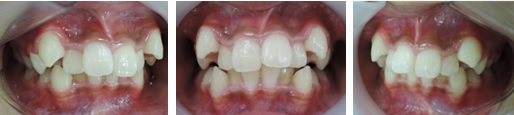

今回の症例は、悪い歯並びの代表例である八重歯です。

歯並びが悪いだけでなく、困ったことに犬歯から奥歯にかけて歯が嚙み合っていない開咬の状態です。

一般的な矯正の治療法では中心から4番目の歯を抜いて隙間をつくり、飛び出した犬歯を並べて治療します。

しかし、この矯正方法は歯を横に動かす治療法なので、噛んだときにできる奥歯の上下の隙間を治すのが苦手です。

当院ではマルチループ(MEAW法)という上の写真で装着しているようなクネクネ曲がったワイヤーを使用して、上下の隙間を埋めていくことで歯並びを整えます。